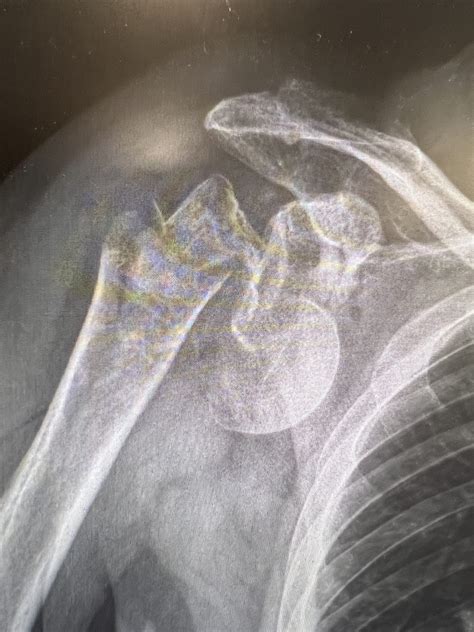

A humeral neck fracture represents a significant orthopedic injury occurring at the proximal end of the upper arm bone, specifically near the shoulder joint. This type of break often results from high-energy trauma, such as a motor vehicle accident, or low-energy falls, which are increasingly common in individuals with reduced bone density or osteoporosis. Because the humerus plays a critical role in shoulder mobility and arm function, understanding the mechanics, diagnosis, and recovery process of this injury is essential for patients navigating the road to rehabilitation.

The proximal humerus is the rounded head of the arm bone that fits into the glenoid cavity of the scapula. A humeral neck fracture can be categorized based on whether it occurs at the anatomical neck (just below the joint surface) or the surgical neck (below the tuberosities). Most fractures are classified using the Neer system, which evaluates the displacement and number of segments involved. When the bone breaks into multiple pieces, the stability of the shoulder joint can be severely compromised.

When a physician suspects a humeral neck fracture, the diagnostic journey typically begins with a physical examination to check for nerve function and blood flow. Imaging is the gold standard for confirmation. X-rays are usually the first step, providing clear images of the bone fragments. In more complex cases where fragments are not clearly defined, a CT scan may be ordered to assess the degree of displacement and help the surgical team plan the best course of action.